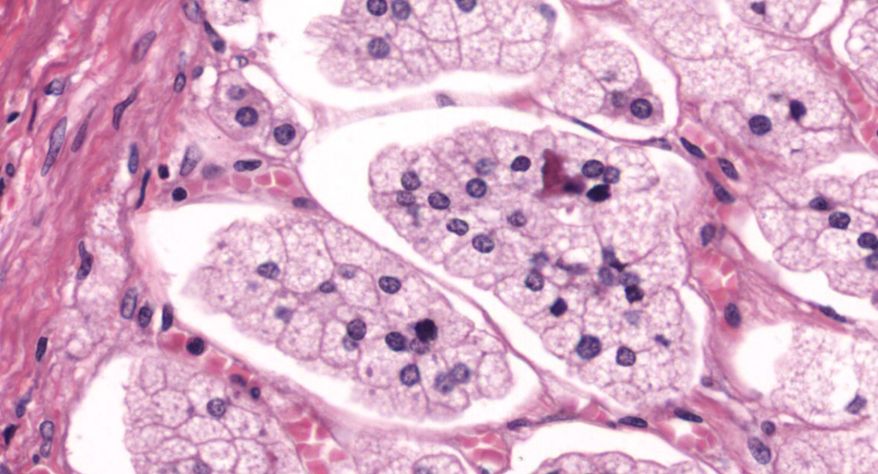

低倍镜观察:1. 被膜:由薄层结缔组织组成。2. 实质:由许多大小不等的滤泡构成。滤泡壁是单层立方上皮细胞,滤泡腔内充满粉红色匀质胶状物,滤泡之间的结缔组织内有丰富的血管。高倍镜观察:1. 滤泡:滤泡壁的单层滤泡上皮细胞一般呈低柱状或立方状,胞质着浅色,细胞核呈圆形。滤泡腔内充满了粉红色匀质胶质。2. 滤泡旁细胞:体积较大,呈圆形或椭圆形;细胞核较大,呈圆形,着色较浅,细胞质染色也较浅。细胞或嵌在滤泡壁上或成团分布于滤泡之间。3. 间质:由结缔组织组成。位于滤泡之间。其中含有丰富的毛细血管及三五成群的滤泡旁细胞。

1.全景图

2.滤泡

3.滤泡上皮细胞

4.胶质

5.滤泡旁细胞1

7.滤泡旁细胞2